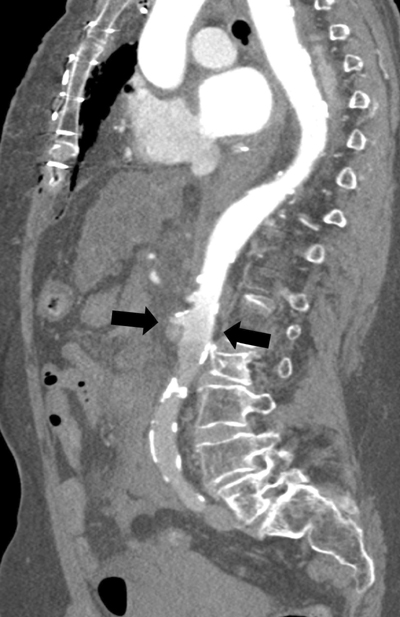

Figure 4

Parasagittal reformatted image of the watershed zone (black arrows) at the level of the superior mesenteric artery (SMA).